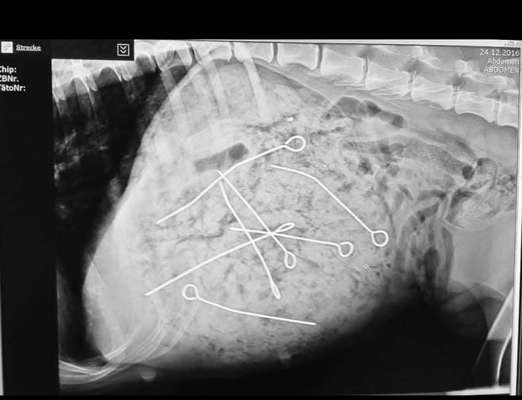

Viele von Hunden aufgenommene Fremdkörper (auch scharfkantige!) können endoskopisch geborgen werden, was für den betreffenden Hund natürlich (im Vergleich zu einer OP) eine sehr attraktive Lösung darstellt. Dazu muss man so ein Teil aber erst mal mit dem Endoskop finden und zu packen bekommen. Genau das kann in einem Magen voller Sauerkraut-Pampe zu einem echten Problem werden. Wir hatten damit in der Vergangenheit (Achtung! Ironie!) schon sehr viel Freude!

Noch schlimmer, wenn das Sauerkraut einen Fremdkörper entsprechender Größe tatsächlich erfolgreich umwickelt und in den Darm bugsiert, wo man mit dem Endoskop irgendwann nicht mehr rankommt. Dann kann durchaus eine Enterotomie, also eine chirurgische Eröffnung des Darms, notwendig werden, um den Fremdkörper entfernen zu können. Die Eröffnung eines Darmabschnitts, in dem sich neben dem Fremdkörper auch noch jede Menge Sauerkraut rumtreibt, ist eine chirurgische Sauerei ersten Ranges mit hohem Komplikationspotenzial.